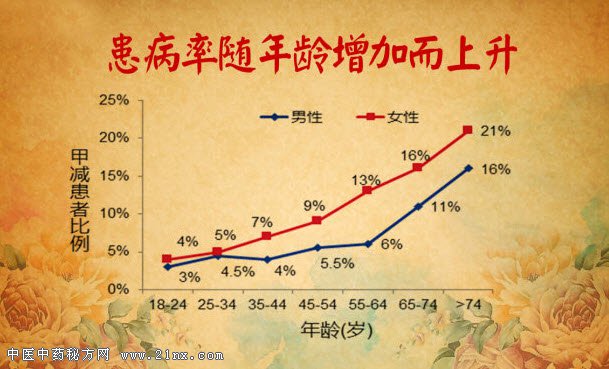

图:患病率随年龄增加而上升 20160717养生堂视频和笔记:唐熠达,心律失常,心梗,心衰,甲状腺 |